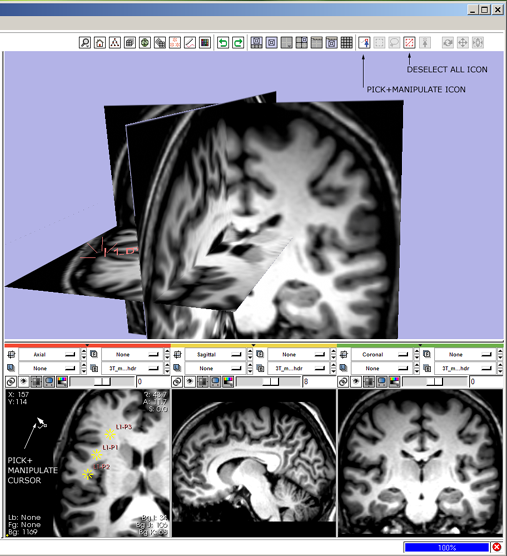

| + | 6(novice) '''select and move fiducials:''' click the mouse-pick-and-manipulate icon [[image:ToolbarMouseManipulate.png]] | ||

* --> mouse-pick-and-manipulate icon highlights, all others deselect, cursor changes to indicate mouse-pick-and-manipulate mode. | * --> mouse-pick-and-manipulate icon highlights, all others deselect, cursor changes to indicate mouse-pick-and-manipulate mode. | ||

* move mouse to location of fiducial in a Slice Viewer and see the fiducial highlight; left-Click and drag in a Slice Viewer to reposition the fiducial point. | * move mouse to location of fiducial in a Slice Viewer and see the fiducial highlight; left-Click and drag in a Slice Viewer to reposition the fiducial point. | ||

* move the mouse away from the fiducial and see it lowlight. | * move the mouse away from the fiducial and see it lowlight. | ||

| − | 7 '''pan the slice view:''' click the mouse-track icon [[image:ToolbarMousePan.png]] | + | 6(expert) '''pick-and-manipulate fiducials:''' press 1-key to switch into mouse-pick-and-manipulate mode. |

| + | * --> mouse pick-and-manipulate icon [[image:ToolbarMouseManipulate.png]] highlights, and all others deselect; cursor changes to indicate mouse-pick-and-manipulate mode, | ||

| + | * then mouse-over a fiducial point, see it highlight, left-Click and drag to reposition it. Release mouse button and move away, and see the fiducial lowlight. | ||

| + | [[image:SB6.png]] | ||

6(novice) select and move fiducials: click the mouse-pick-and-manipulate icon ![]()

- --> mouse-pick-and-manipulate icon highlights, all others deselect, cursor changes to indicate mouse-pick-and-manipulate mode.

- move mouse to location of fiducial in a Slice Viewer and see the fiducial highlight; left-Click and drag in a Slice Viewer to reposition the fiducial point.

- move the mouse away from the fiducial and see it lowlight.

6(expert) pick-and-manipulate fiducials: press 1-key to switch into mouse-pick-and-manipulate mode.

- --> mouse pick-and-manipulate icon

highlights, and all others deselect; cursor changes to indicate mouse-pick-and-manipulate mode,

highlights, and all others deselect; cursor changes to indicate mouse-pick-and-manipulate mode, - then mouse-over a fiducial point, see it highlight, left-Click and drag to reposition it. Release mouse button and move away, and see the fiducial lowlight.